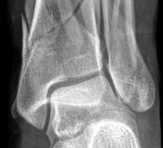

A 38-year-old woman was involved in a motor vehicle accident. She experienced immediate pain and noticed her left lower extremity was deformed. In the emergency department, x-rays showed a displaced metaphyseal fracture of the distal tibia with articular involvement (AO/OTA 43C3.3(5b) with a 4F3B fibular fracture), and posterior dislocation of the tibiotalar joint (Fig 2.2-1). The fracture was closed.

Fig 2.2-1a–b Immediate postinjury x-rays.

1. Comminuted pilon fracture (AO/OTA 43C3.3[5b]) with 4F3B fibular fracture (AP view).

2. Posterior dislocation of the tibiotalar joint (lateral view).